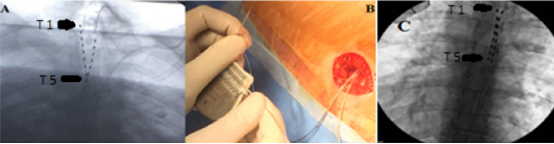

電極植入